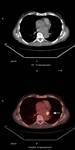

Methods: Twenty-two patients referred to our department with a suspected cardiac mass, previously detected by cardiac ultrasound, were evaluated by CT (12 patients) and MRI (4 patients). Six patients were examined by both modalities. In 2 cases of staging of a known primary neoplasm and one case of a suspected epicardiac lesion, positron emission tomography (PET-CT) was performed. The CT cardiac examinations were performed using a 16-slice multislice scanner with ECG gating. The MRI examination was performed on a 1.5 Tesla MRI scanner using an ECG-gated cardiac protocol and the PET-CT examination was performed on an integrated PET-CT four-slice scanner, using 370 mMBq of fluorodeoxyglucose.

Results: Twenty-two cardiac masses were successfully detected and their characteristics adequately delineated, including eight myxomas, one angiosarcoma, one ventricular lymphoma, one endocardiac metastasis, one epicardiac paraganglioma, and 10 cases of intracardiac thrombi.